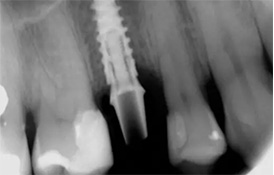

在AI智能设计软件中,医生能详细测量牙槽骨的密度、高度、宽度等条

件,设计最佳力学种植点,标记血管与神经等危险区域,精确模拟并重

建咬合关系,完成以修复为导向的种牙方案设计,同步完成导板设计。

MAC数字化精确导板辅助

借助精确打印的3D导板辅助工具,麦芽的医生在种牙中,能精确定位植入 路径,避免传统种牙需翻瓣暴露视野的弊端,从而提升了安全性、缩小了 创口、优化了种牙体验。